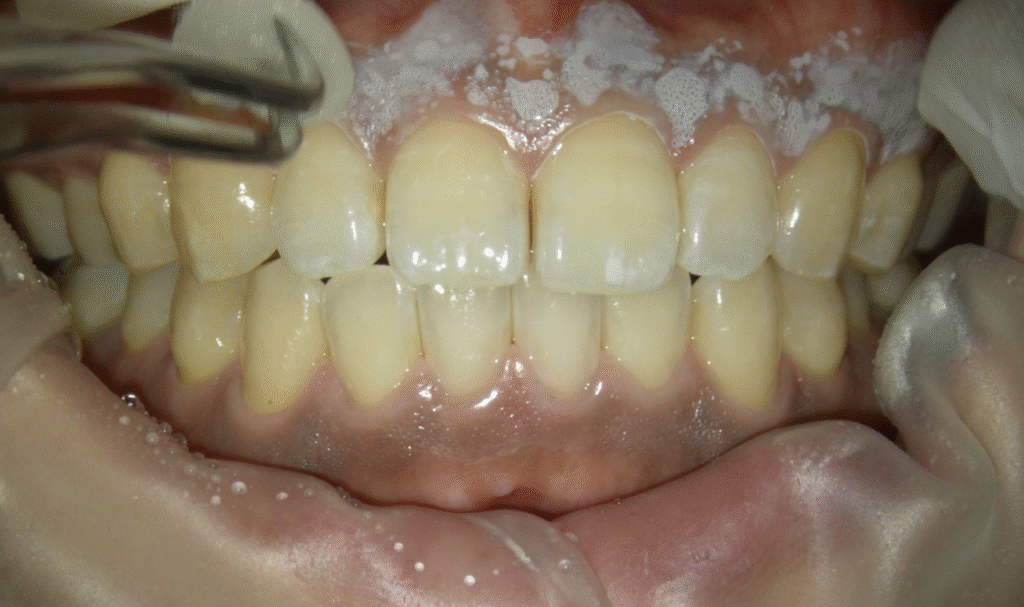

2. フェノール系薬剤の塗布

まず、メラニン色素が沈着している歯茎の部分(角化歯肉)に、フェノール系の薬剤を慎重に塗布します。

薬剤が歯茎の表面に作用することで、

皮膚の浅い部分に軽度の化学やけどが起こります。

この時の痛みはほとんどありません

3. 大量の水で洗う

塗った部分の色が変わったら大量のお水で洗います。以前はアルコールで拭くことも推奨されていましたが、中和効果はなく、大量の水で洗うのが確実です🚿